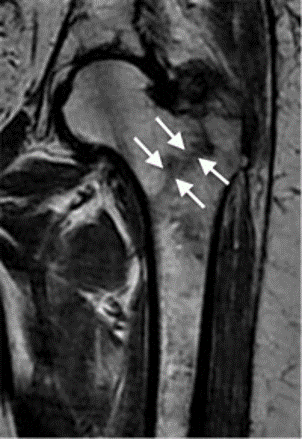

Magnetic resonance imaging (MRI) scans. MRI scans are rarely needed. An MRI scan provides detailed images of both soft tissues and bone. Because it is very sensitive, an MRI can sometimes detect a small or incomplete fracture that cannot be seen on an X-ray. MRI is more commonly ordered if both X-rays and CT scans are negative and if your doctor suspects a stress fracture.

hip fracture

This MRI scan shows a hip fracture that was not visible on an X-ray.